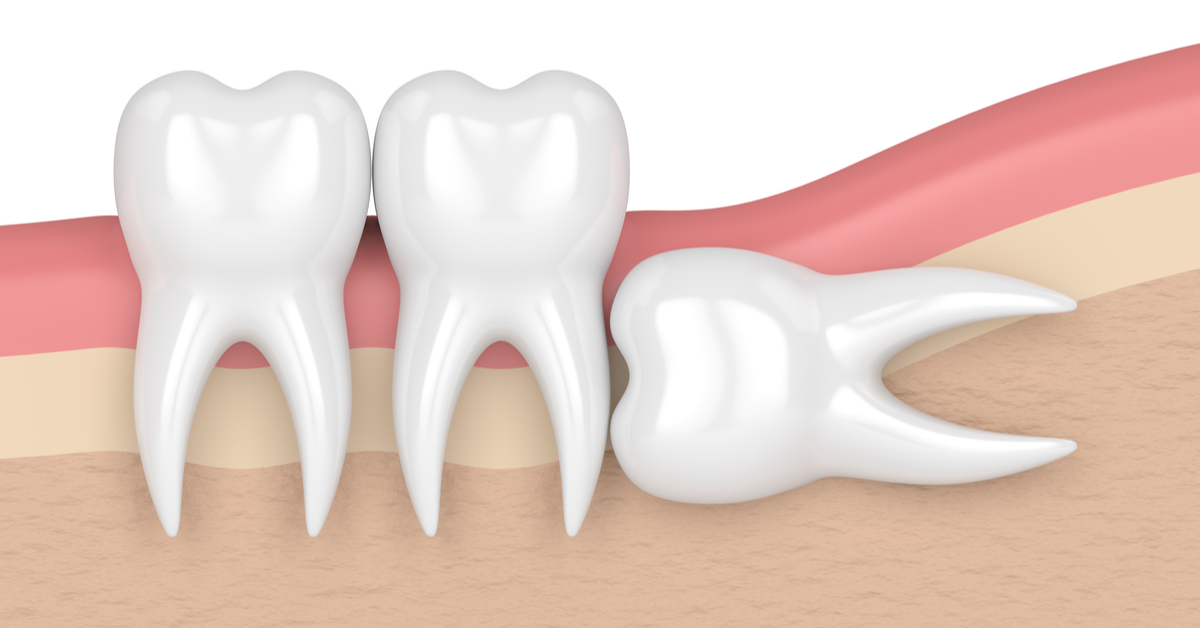

حالة من الرعب يدخل فيها الكثير عندما يكون أمام مرحلة الدخول في عملية خلع ضرس العقل.. بل يفضل الكثير تحمل الآلام على أن يخلع الضرس، وفي هذا التقرير سوف نعرض كم تستغرق عملية خلع ضرس العقل، فهو ينمو خلال الفترة العمرية من 17 سنة حتى 30 سنة، ويكون عبارة عن 4 ضروس في كل جهة اثنين، واحدة في الفك السلفي والآخر علوي.

- إذا كانت جذور ضرس العقل شديدة الانحناء.

- وكذلك مع حالات ضرس العقل المدفون.